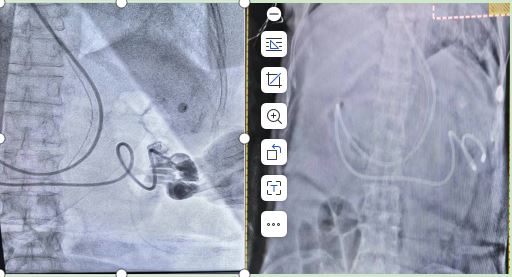

该项技术不需任何仪器辅助,难点就在于如何准确地让鼻空肠管通过幽门到达空肠,对操作者要求较高,需要娴熟的技术、稳定的心态、丰富的临床经验,在一切准备充足后,徐利护士长带领护理团队成功将鼻空肠管经过鼻、食管、胃部、幽门、十二指肠置入到空肠位置,经过听诊初步确定鼻肠管位置准确,蒋万里医生团队首次先用彩超确认位置,2月3日早9点,患者床旁DR显示鼻肠管置管位置大于2个锥体,总平分大于5分,基本确认鼻空肠管置入到位,由于是我科首次,主任本着认真负责的态度,患者在医护人员陪同下,在DSA下造影确认,“金标准”证实我科首例床旁徒手盲插鼻肠管置管术置管成功,为患者建立了补充营养的路径,满足患者疾病治疗的需求,提高患者生活质量,开辟了营养新渠道,同时也是重症医学科对患者营养支持护理水平一次新的突破!